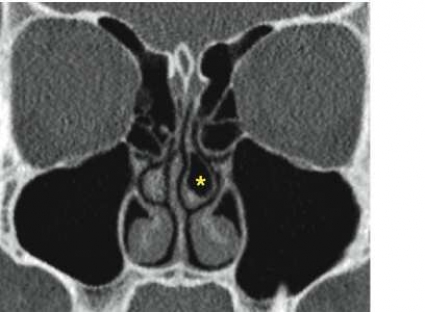

Relevanta bifynd. Concha bullosa, som kan vara en bidragande orsak till sinuit, påvisades i 8 fall, och Haller-cell, som kan orsaka en anatomisk trängsel i infundibulum, påvisades i 1 fall. Postoperativa förändringar, huvudsakligen status efter resektion av processus uncinatus, påvisades i 7 fall. I 1 fall hittades en sellaförstoring, vilket ledde till att man kunde påvisa ett hypofysadenom, och i 1 fall fann man en inflammatoriskt betingad bendefekt i framväggen av frontalsinus. Förutom sellaförstoringen hade inget av dessa relevanta bifynd kunnat påvisas med vanlig röntgenundersökning av bihålorna.

Användandet av lågdos-DT innebär sålunda inte bara en säkrare diagnostik av bihåleförändringar än med vanlig röntgenundersökning, utan man får också viktig tilläggsinformation, som inte kan erhållas med vanlig röntgenundersökning. Även möjligheten att visualisera små, men kliniskt relevanta anatomiska avvikelser (tex concha bullosa, Haller-celler och dysplasier), postoperativa förändringar, benförändringar vid kronisk sinuit och odontogena orsaker till sinuit, gör lågdos-DT klart överlägsen konventionell röntgenundersökning vid sinuit (Figur2).